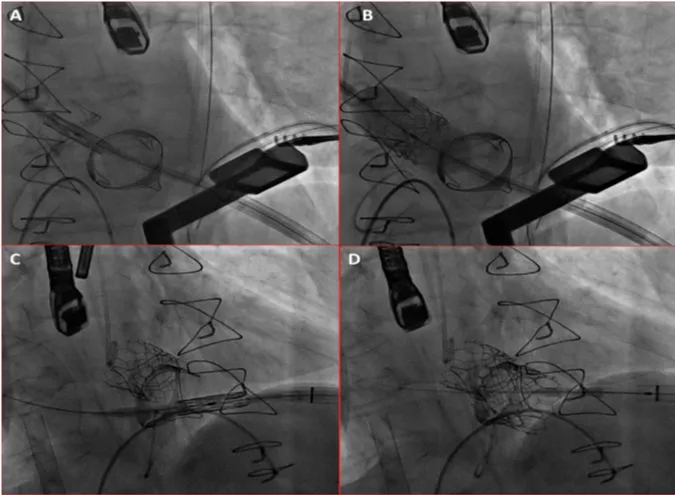

We report a 72 years old male patient case with past history of surgical aortic and mitral biological valves replacement with tricuspid ring in 2010. The patient presented severe dyspnea New York Heart Association (NYHA) class IV with stenotic aortic and mitral bio prostheses and left ventricle ejection fraction of 30%. The patient had no cardiovascular risk factor and received vitamin K antagonist (VKA) for persistent atrial fibrillation. Trans esophageal echocardiography (TEE) showed a severe aortic bioprosthesis stenosis with a mean aortic gradient of 32 mmHg, the estimated surface was 0.6 cm2 and a severe mitral bioprosthesis stenosis with a mean gradient of 20 mmHg, the estimated surface was 0.9 cm2 and pulmonary hypertension of 65 mmHg. TEE revealed the presence of a voluminous thrombus appended in the left atrium despite optimal anticoagulation (target INR stable between 2-3). The patient was screened for a double valves in valves procedure, coronary angiogram did not reveal significant coronary stenosis. We repeated the TEE after one month with the ad of aspirin on top of VKA to reduce the left atrial thrombus without success (Figure 1A). Heart team decision was to perform valves in valves (VIV) aortic and mitral replacement via transapical access due to the contra indication to use the transeptal access for the mitral bioprosthesis VIV. We planned this procedure with cardiac computed tomography (CT), 3-dimension reconstruction and VIV implantation simulation (Figure 1B). To rule out the high risk of stroke emboly during the procedure we involved interventional neurologist to perform cerebral angiography just after VIV implantations. The procedure was performed under general anesthesia with arterial femoral access 6F and venous femoral access 7F to introduce a temporary pacemaker. The transapical access was complicated with right ventricle laceration an urgent peripheral arteriovenous extracorporeal membrane oxygenation (ECMO) was implanted to unload the right ventricle and perform the hemostasis with success. Thereafter, we performed first a VIV implantation with an Edwards Sapien n°3 26 mm in aortic position and VIV implantation with an Edwards Sapien n°3 29 mm in mitral position without complication (Figure 2). Cerebral angiography did not showed occlusion of main cerebral arteries. ECMO was removed the same day and patient was discharged at home after 14 days relief of symptoms and without adverse neurological outcome. At 6 months follow up, patient was asymptomatic with stable mean gradients of 11 mmHg for the aortic VIV and 7 mmHg for the mitral VIV, left ventricle ejection fraction was 45%. Controlled CT showed thrombus regression and 3-dimension reconstruction was similar to the simulation.

Figure 1: A: Tran’s esophageal echocardiography showing left atrial thrombus. B: 3 dimension cardiac computed tomography reconstruction with valve in valve implantation simulation.